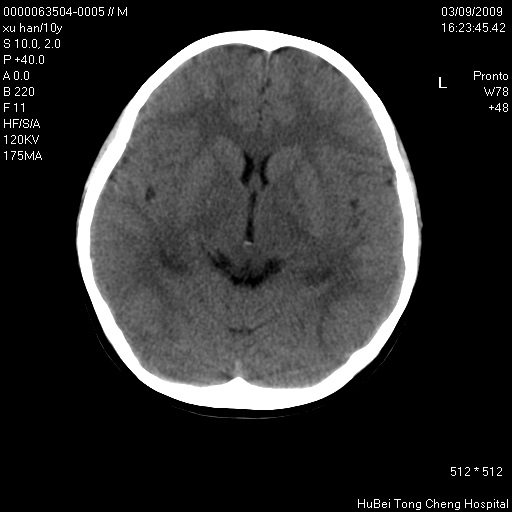

以下是引用道哥在2009-3-9 18:40:00的发言:[br]未见明显异常,必要时mr(dwi)成像。

以下是引用余辉在2009-3-10 11:01:00的发言:[br]考虑双侧海马急性缺氧性损伤